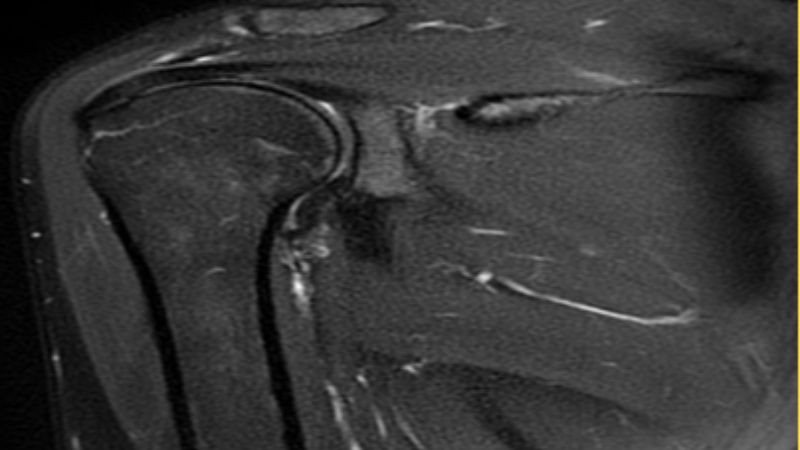

Chụp cộng hưởng từ (MRI)

Chụp cộng hưởng từ giúp đánh giá mức độ nặng cũng như nguyên nhân dẫn tới hội chứng chóp xoay vai. Phương pháp này cung cấp thông tin về các vấn đề như:

- Có rách vòng xoay vai không?

- Kích thước và vị trí vết rách.

- Thoái hóa khớp.

- Viêm bao hoạt dịch.

- Đánh giá tính toàn vẹn của khớp.

Cộng hưởng từ giúp đánh giá phần mềm tại khớp vai hiệu quả